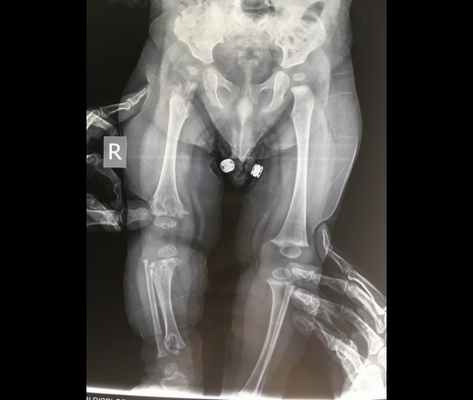

Лабораторные данные. Рентгенограммы. На рентгенограммах черепа обнаружены лобный и затылочный гиперостозы и/или склероз. Основание черепа обычно плотное с облитерированными параназальными синусами и с недостаточной пневматизацией сосцевидного отростка. Отмечается гипертелоризм. В течение первых 6 лет жизни метафизы длинных костей начинают приобретать булавовидную форму, выраженную значительно слабее, чем это наблюдается при болезни Пиле (метафизарной дисплазии), и могут быть на протяжении раннего детства минимальным и. У маленьких детей и в старшем возрасте встречается диафизарный склероз, но с возрастом он исчезает (Beckman, Walker). В коротких трубчатых костях обнаруживаются те же самые изменения, что и в длинных костях. Может быть расширена грудинная половина ключиц. Таз и латеральная часть позвоночника нормальные. В некоторых случаях отмечается сужение внутреннего слухового прохода (Rimoin et al.). Политомограммы показали, что область улитки заполнена костью (Gladney, Monteleone).

Краниометафизарная дисплазия - остеохондродисплазия, характеризующаяся гиперостозом и склерозом черепно-лицевых костей и расширением метафизов. Часто данное заболевание принимают за болезнь Пайла (множественную метафизарную дисплазию), однако при краниометафизарной дисплазии наблюдается более выраженный гиперостоз черепа и меньшее расширение метафизов. Для заболевания характерно утолщение свода и склероз основания черепа, утолщение костей лицевого черепа, макроцефалия, относительно короткий нос, отличительным признаком является толстый костный выступ над переносицей. У пациентов наблюдается гипертелоризм глаз, экзофтальм, сдавление черепных нервов, головная боль, узкие носовые ходы и заложенный нос. В конечностях отмечается легкое или умеренное расширение и склероз метафизов, наиболее заметные на дистальном конце бедренной кости, Х-образное искривление ног.

Это аутосомно-доминантное заболевание Аутосомно-доминантные Генетические нарушения, вызванные изменениями в одном гене («Менделевские нарушения»), являются самыми простыми для анализа и наиболее хорошо поняты. Если экспрессия признака требует только. Прочитайте дополнительные сведения человека обусловлено мутациями гена ANKH. В раннем детстве образуются параназальные бугры, а также прогрессирующее расширение и утолщение костей черепа и нижней челюсти, что приводит к деформации лица и челюсти. Поражение костей вовлекает черепные нервы, вызывая дисфункцию. Исправление прикуса зубов Неправильный прикус Неправильный прикус является ненормальным контактом между зубами верхней и нижней челюсти. (См. также Обследование пациентов со стоматологическими заболеваниями [Evaluation of the Dental Patient]. Прочитайте дополнительные сведенияДиагноз краниометафизарной дисплазии предполагается при наличии типичных черепно-лицевых аномалий, которые иногда сочетаются с повышенной восприимчивостью к респираторным инфекциям, или нарушение может быть обнаружено во время оценки дисфункции черепных нервов, которые могут возникнуть в результате защемления у основания черепа. Как правило, проводят обычное рентгенологическое исследование. Рентгенологические изменения являются возрастными и обычно проявляются в возрасте 5 лет. Склероз является главной особенностью черепа. В трубчатых костях отмечаются булавовидные расширения метафизов, особенно в области дистальной части бедренной кости. Однако, эти изменения являются менее серьезными, чем при болезни Пайла Метафизарная дисплазия (болезнь Пайла) Краниотубулярные дисплазии включают минимальный остеосклероз с нормальным формированием скелета. Остеопетроз является наследственным заболеванием, характеризуется повышенной плотностью костной. Прочитайте дополнительные сведения . Позвоночник и таз не поражены.

Краниометафизарная дисплазия аутосомно-рецессивного типа характеризуется намного более выраженными пороками развития костей черепа и конечностей, признаки патологии часто выявляются сразу после рождения ребенка. У больных присутствует выраженный гипертелоризм, черты лица зачастую крайне несимметричны, деформации переносицы и носа могут приобретать признаки уродства. В ряде случаев наблюдаются макроцефалия, нижнечелюстной прогнатизм, другие нарушения прикуса и расположения зубов. По мере роста больного аномалии костей черепа могут усугубляться. Метафизы костей конечностей резко расширены, что нередко обуславливает вторичные деформации (например, Х-образное искривление ног). Как и в предыдущем варианте, при этой форме краниометафизарной дисплазии часто возникают разнообразные неврологические нарушения, вызванные сдавлением и травматизацией черепно-мозговых нервов. Они могут проявляться глухотой, нарушениями зрения, расстройствами кожной чувствительности на лице, парезом мимической мускулатуры и головными болями. Существуют отдельные описания больных, одновременно страдающих краниометафизарной дисплазией и умственной отсталостью, однако достоверных данных о взаимосвязи этих двух состояний на сегодняшний день нет.

Намного больше информации при краниометафизарной дисплазии дают рентгенологические методы исследования скелета. На рентгенограммах черепа при аутосомно-доминантной форме заболевания определяются уплотнение костной ткани в области затылочной кости, склероз основания черепа, пониженная пневматизация синусов и ячеек височной кости. В ряде случаев может выявляться склероз межкостных швов и расширение метафизов трубчатых костей. При аутосомно-рецессивном типе краниометафизарной дисплазии на рентгенограммах обнаруживаются схожие, но намного более выраженные нарушения, например – полное отсутствие околоносовых пазух, резкое сужение и иногда заполнение костной тканью отверстий черепно-мозговых нервов. Кроме того, наблюдается склероз не только основания, но и свода черепа, в ряде случаев определяются значительные деформации костей лицевого отдела. Немного сильнее, чем при доминантном типе, выражены расширение и склероз метафизов трубчатых костей.